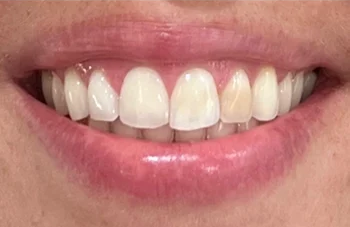

Onlangs bezocht een patiënte van in de dertig onze praktijk. Haar mondgezondheid en mondhygiëne waren uitstekend. Er was maar een ding dat opviel en waar zij niet tevreden over was: frontelement 22 was significant donkerder van kleur

Afbeelding 1: Uitgangssituatie vóór de bleekbehandeling

Bij de eerste kleurbepaling van dit element (22) was er sprake van kleurtint A3.